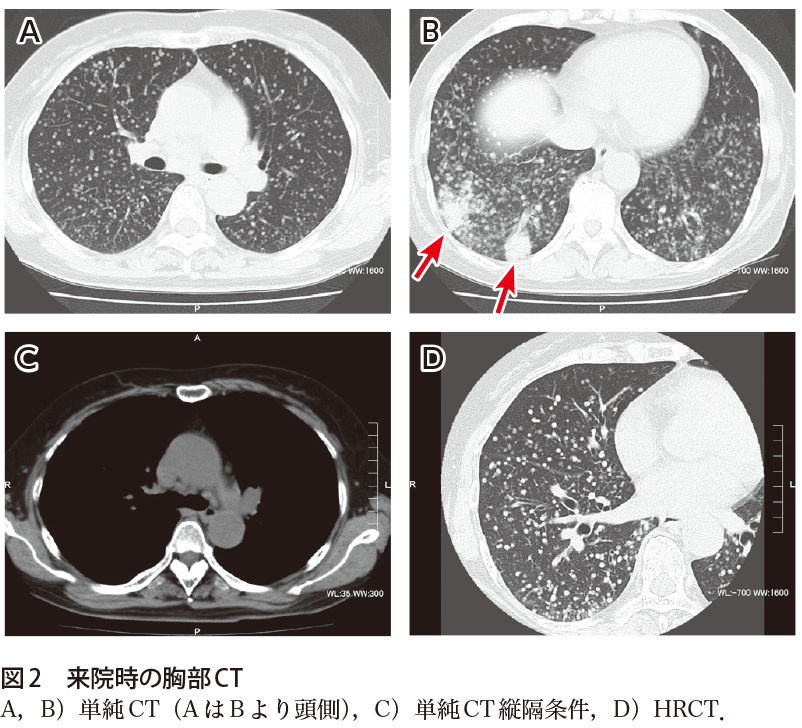

分化度は腫瘍の大部分を占める方の組織型の分化度とする。 The tumor recurred in the femur 7 months after the operation, and the patient died 16 months after the operation. A 61-year-old man was given a diagnosis of pneumonia and was given a course of antibiotics at another hospital. 内部が壊死しているのは転移性の特徴。